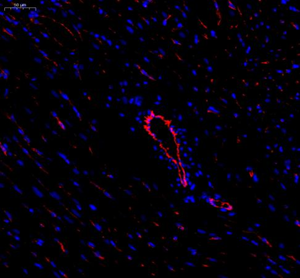

| IF analysis of CD31 (GB12063). Sample: Mouse heart (Paraffin), 4% PFA (G1101) 12-24h. Antigen retrieval: Citrate buffer (pH 6.0) (G1201), pressure cooker 2min. Blocking buffer: 3% BSA in PBS (GC305010), RT, 30min. Primary antibody: 1: 600, 4°C overnight. Secondary antibody: Cy3 conjugated Goat Anti-mouse IgG (H+L)(GB21301),1: 200 RT 1h. |

| IF analysis of CD31 (GB12063). Sample: Rat heart (Paraffin), 4% PFA (G1101) 12-24h. Antigen retrieval: Citrate buffer (pH 6.0) (G1201), pressure cooker 2min. Blocking buffer: 3% BSA in PBS (GC305010), RT, 30min. Primary antibody: 1: 600, 4°C overnight. Secondary antibody: Cy3 conjugated Goat Anti-mouse IgG (H+L)(GB21301),1: 200 RT 1h. |